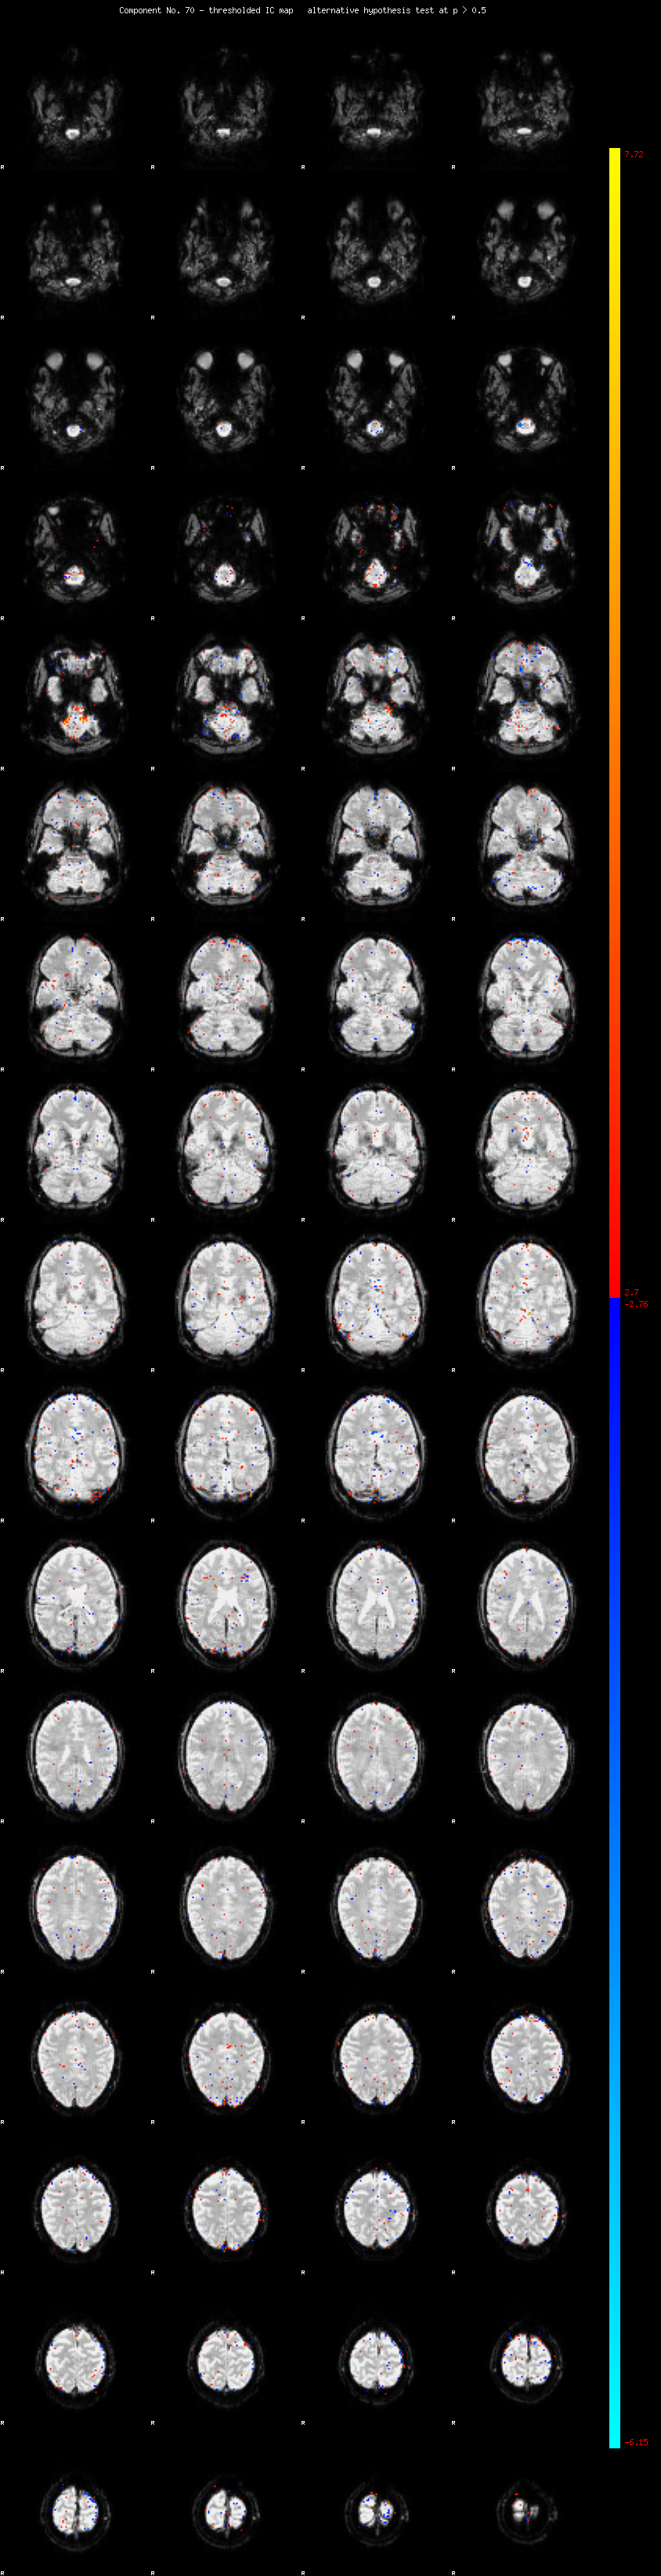

MELODIC Component 70

0.78 % of explained variance;     0.51 % of total variance

MMfit